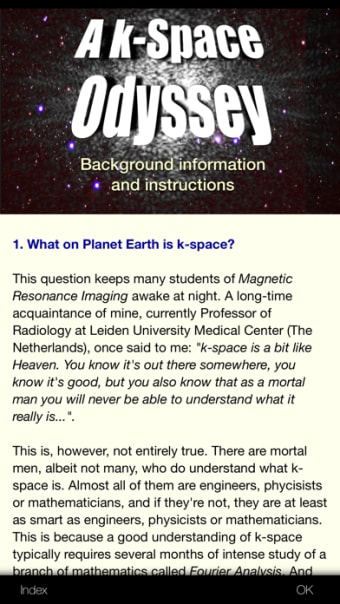

EltjoHaselhoffによるiPhone用のフルバージョンアプリ。

K-Space Odyssey strong>はiPhone用のフルバージョンのアプリで、カテゴリの一部になっています。医学'。

iPhone用K-Spaceオデッセイについて

このソフトウェアは2019年8月23日にSoftonicで公開されており、まだ試すことができませんでした。 p>

ぜひお試しいただき、コメントを残すか、ウェブサイトで評価してください。これは、残りのユーザーの多くに役立ちます! p>

K-Space Odysseyは、iOS12.1.2以降で利用できます。ソフトウェアの現在のバージョンは1.9.1であり、英語でのみ入手できます。 p>